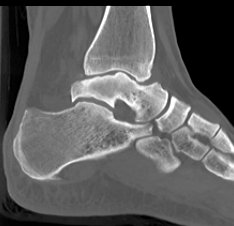

CT

Talus ACN CT 1Talus AVN CT 2